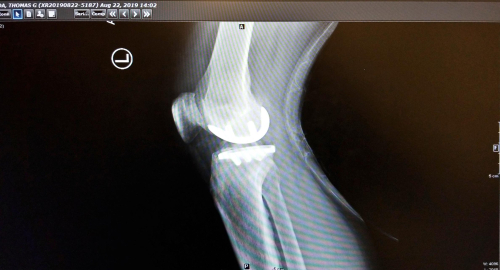

This is the appliance inside the knee – that’s me!

And how things looked August 22nd, eight days after the surgery and the outer dressing off.